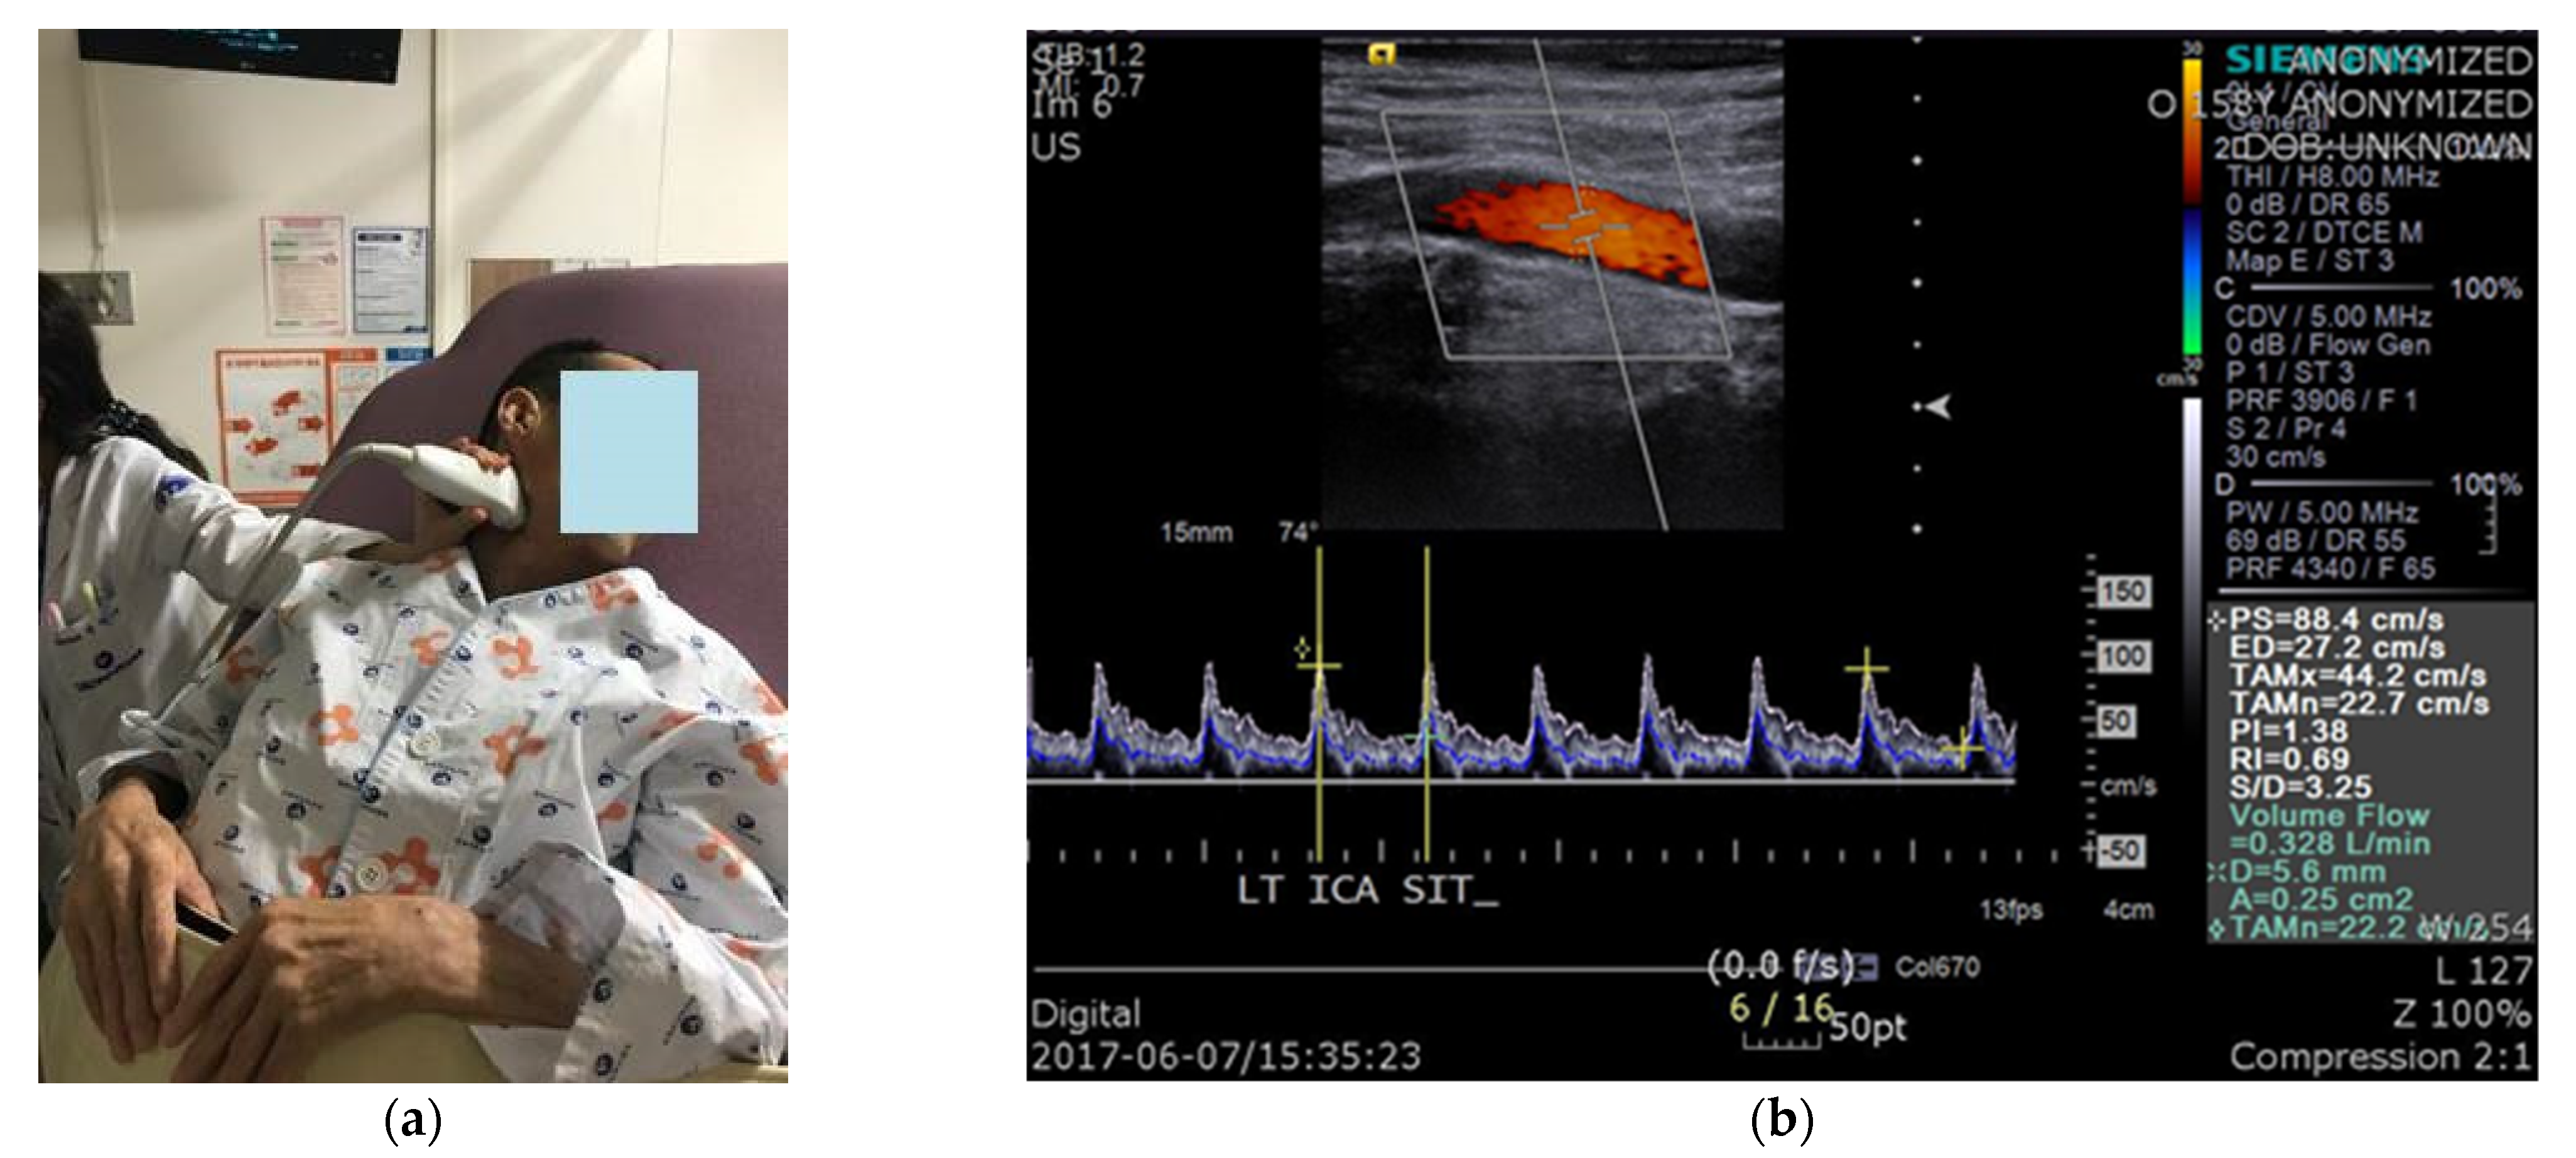

We conducted CDU during head-up tilt in patients with a CSCI. The ICA was studied on both sides, and intravascular flow volumes were calculated using a 9-MHz linear array transducer. BFV measurements were automatically calculated by the built-in software of the ultrasound device (Siemens ACUSON, Siemens Healthcare, Erlangen, Germany). For flow-volume measurements, the head was turned 25°–40° to the contralateral side, and a straight segment of the ICA, at least 2 cm above the carotid bulb, was selected (Figure 1). Measurements were performed on a horizontal segment in the sagittal plane. The arterial diameter was calculated as a vertical line through the lumen between the echogenic intimal layers. The value obtained from the test is volume flow rate, which was automatically calculated from the cross-sectional area of the blood vessel and the time-averaged mean velocity: volume flow rate = area (cm2) × time-averaged mean velocity (cm/s). The peak systolic velocity, end diastolic velocity, time-averaged mean velocity, vessel diameter, and vessel area were all measured during the test. All patients were allowed to rest on the examination table for 5 min before the test. CBFV, BP, and heart rate (HR) were measured in the supine position, immediately after the patient was tilted by 50°, and 5 min after the tilt. To increase the reliability of the test, CBF was measured three times in each position, and the mean value was used. In addition, the presence or absence of presyncopal symptoms, such as dizziness, light-headedness, nausea, and blurry vision, in each position, was recorded.

Figure 1. Carotid duplex sonography: (a) The position of the patient and measurements of cerebral blood flow using carotid duplex ultrasonography; (b) The value of interest in the test was volume flow.